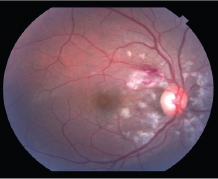

The patient followed up 3 days later complaining of para central scotoma and visual acuity of 20/30 in the right eye. At this time, the dilated exam revealed pronounced, peripapillary yellow-white patches consistent with Purtscher flecken and cotton wool spots in the right eye only. There was also an intraretinal hemorrhage along the superior arcade and an abnormal foveal reflex in the affected eye. With this constellation of findings, Purtscher’s retinopathy was diagnosed and the decision was made to observe for clinical improvement. Given the clinical diagnosis, fluorescein angiography was deferred.

Figure 1A: Fundus photo right eye 3 days after the accident showing polygonal white lesions in a peripapillary distribution, and area of intraretinal hemorrhage along the superior arcade.

Figure 1B: Fundus photo of the right eye 10 days after the accident showing similar, more defined white lesions.